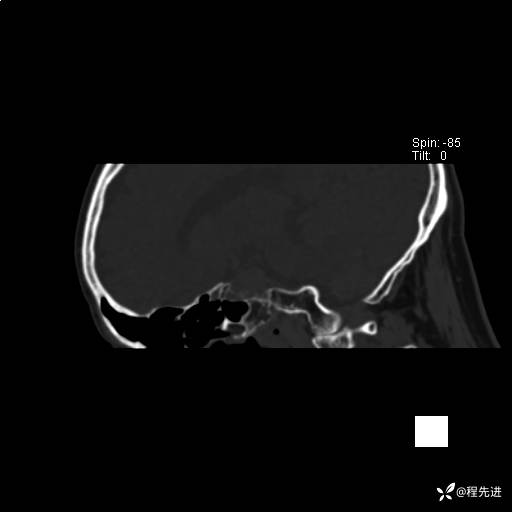

患者性别:男

患者年龄:74岁

简要病史:出现视物重影2月余,未予重视,2月来症状逐渐加重

实验室检查:无特殊

CT平扫: